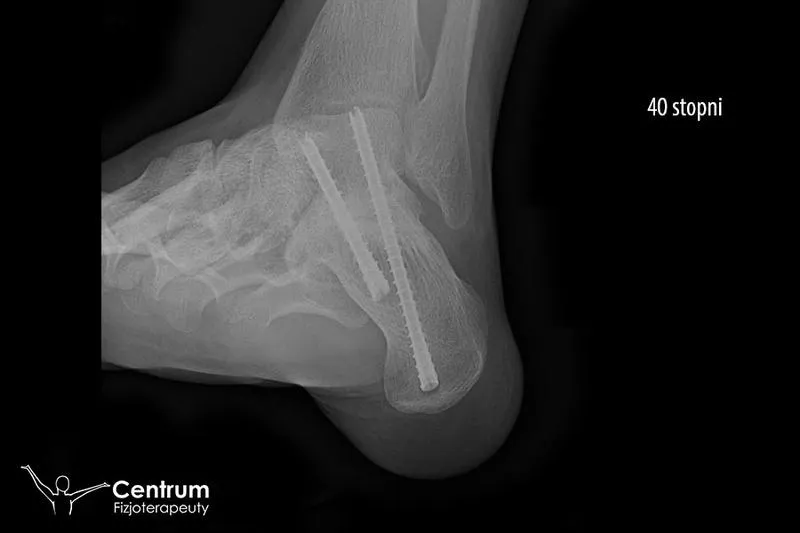

Kiedy dochodzi do skręcenia, mamy do czynienia z naciągnięciem lub rozerwaniem więzadeł oraz uszkodzeniem torebki stawowej. Szacuje się, że takie urazy występują w trzech stopniach zaawansowania – im wyższy stopień, tym gorsze konsekwencje. W najłagodniejszych przypadkach czasami wystarczy kilka dni odpoczynku, stosowanie lodu oraz wsparcie w postaci stabilizatora. W przypadku poważniejszych urazów może być konieczna terapia manualna, kinesiotaping, a nawet operacja. Krótko mówiąc, zdrowie stawu skokowego kluczowo wpływa na naszą mobilność; jego usprawnienie pozwala uniknąć „głupich” powrotów do skakania na jednej nodze.